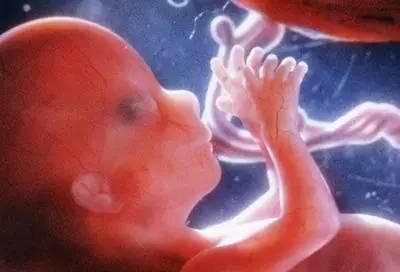

在孕早期和中期,由于胎儿还不是很大,而且此时子宫空间大,羊水量也充足,正是胎儿“大展身手”的时候,胎位随时可以变动,想怎么翻就怎么翻,今天横着、明天竖着都可以,全凭胎宝宝乐意。

到了怀孕七个月,也就是怀孕25-28周这个阶段,胎儿身长大概在35厘米左右,体重大约在1000-1400克,体型还很小巧玲珑的,子宫也还有足够大的空间。

所以,不管胎儿是什么体位,横着也好,竖着也好,都可以说是正常的,也不需要纠正。胎儿自然会通过自己的方法调整过来,且大部分的胎儿都能调整过来,所以孕妈不用担心。